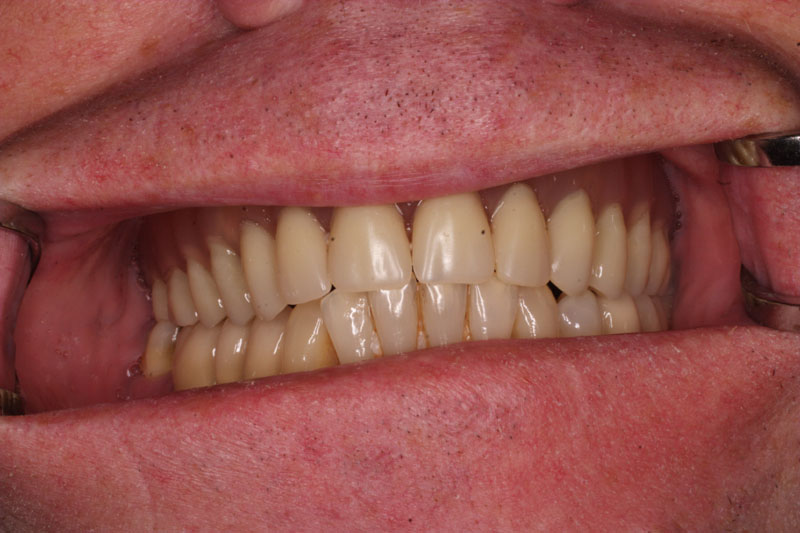

S pomocí zubních implantátů můžeme díky různým kotevním systémům (třmeny, kulové hlavy, Locatory) zajistit stabilitu a držení protézy nebo při použití většího počtu implantátů zhotovit pevné náhrady – můstky nalepené nebo našroubované na pevno na implantáty.

S těmito typy náhrad můžeme dosáhnout perfektní funkci, výbornou estetiku, fonetiku a současně zajistit u pacienta možnost dobré hygienickou péče a čištění, která je pro životnost implantátů velice důležitá.